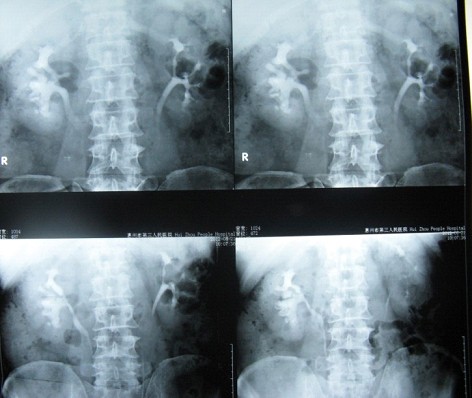

患者鐘某主因“右側(cè)腰部間斷疼痛20余年加重3個(gè)月”入院。如下圖圖1、圖2和圖3所見(jiàn)具備兩個(gè)特點(diǎn):一、結(jié)石復(fù)雜,除主體位于腎盂和中下大盞外,多個(gè)中下小盞內(nèi)還有多發(fā)結(jié)石;二、沒(méi)有腎積水,腎盞杯口不大。

1 術(shù)前KUB平片可以清晰地看到右腎復(fù)雜性鑄型結(jié)石

2 術(shù)前腎靜脈造影可以看到右腎無(wú)積水